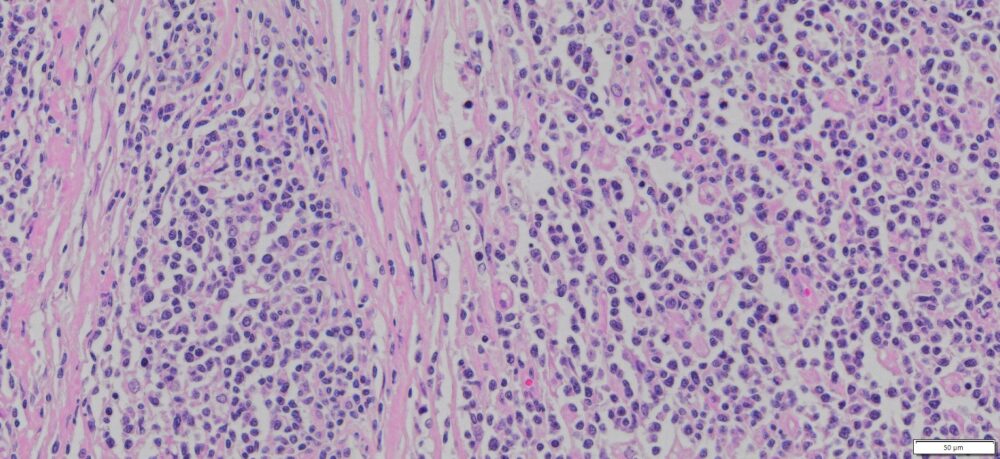

Description

| Tissue | Pathology Diagnosis | Gender/ Age (year) | %Tumor Area | Tumor Grade | TMN/Stage | IHC data |

| Human lymph node | Diffuse Large B-Cell Lymphoma (DLBCL), Treatment Naïve | Male/52 | 85% | N/A | N/A | CD20+, CD3-, MIB Index 65-70% |

Slide Preparation

Human tissue was fixed in formalin immediately after excision and embedded in paraffin. The tissue sections were 5 µm in thickness and mounted each on positively charged glass slides.